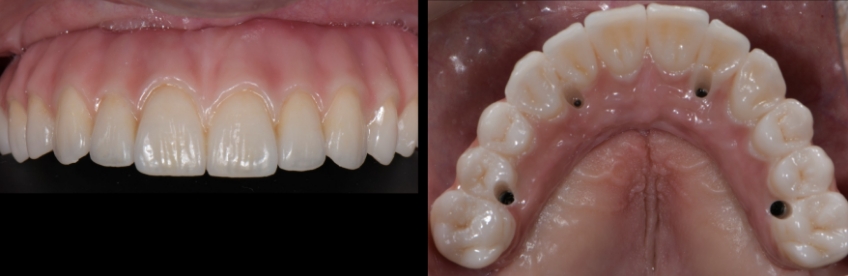

Usually, straight SRA abutments are used with anterior implants when they are parallel. Still, it is not uncommon for the restorative dentist to realize during the prosthetic phase of treatment that the position of the screw access hole could be optimized by changing the angulation of the SRA abutments. Ideally, the treating team aims to have the access holes coming out of the cingulum in anterior implants and the center of the occlusal area in posterior implants.

This visual essay shows, through a series of images, the fabrication of a maxillary implant-supported fixed dental prosthesis. The SRA abutments of the anterior implants were changed to optimize the definitive implant-supported fixed dental prosthesis design.

Suppose we decide to alter the angulation of the SRA abutments. In that case, we can position the access hole more anteriorly, thus increasing the palatal thickness and improving the biomechanics and hygiene access.

In this visual essay, we have outlined the steps in the fabrication of a maxillary full arch implant-supported prosthesis solution where the SRA abutment needs to be changed because the orientation of the screw access hole in the provisional restorations seems too palatal from an ideal position, thereby underlining the importance of analyzing these aspects during the provisional phase and correcting the angulation of them to provide a more ideal design and increase the long term predictability of the prosthetics.